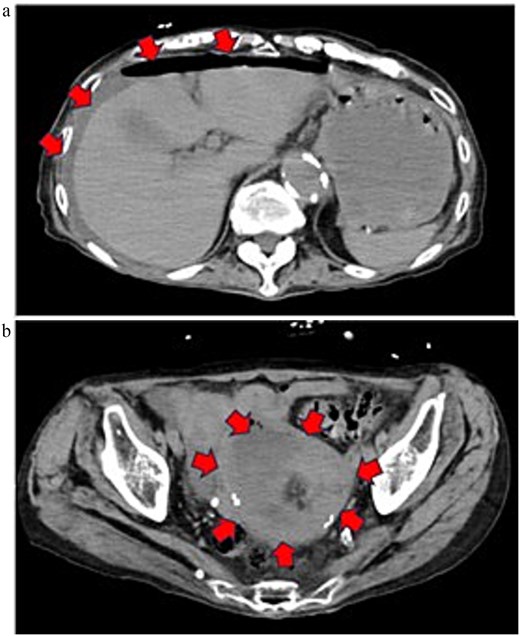

On admission, she was in shock (blood pressure 73/52 mmHg, pulse 113 bpm) with diffuse abdominal tenderness. Laboratory tests revealed marked inflammation (WBC 10.7 × 103/μL, CRP 12.49 mg/dL) and hypoalbuminemia (2.2 g/dL). CT demonstrated massive ascites with free gas and a low-density uterine lesion suggestive of pyometra (Fig. 1).

Preoperative contrast-enhanced CT image (equilibrium phase). (a) Horizontal section. Extensive ascites extending to the liver surface and free gas in the abdominal cavity are noted. (b) Horizontal section. A low-attenuation area suggestive of a retained uterine abscess was identified within the uterus.